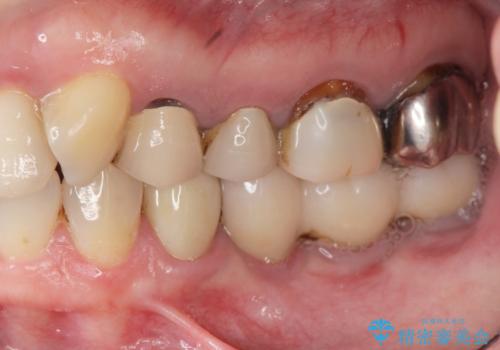

[ 歯ぐきから出血をする ] 歯周外科を伴うセラミックやりかえ治療

![[ 歯ぐきから出血をする ] 歯周外科を伴うセラミックやりかえ治療の症例 治療前](https://seimitsushinbi.jp/wp/wp-content/uploads/2024/12/dad9bd6fd8fdc9454170eb3e86a080a9-500x350.jpg?v=1733474741)

![[ 歯ぐきから出血をする ] 歯周外科を伴うセラミックやりかえ治療の症例 治療後](https://seimitsushinbi.jp/wp/wp-content/uploads/2024/12/39b2ace77ddc630ec8fbb92d0a9c107d-500x350.jpg?v=1733474802)